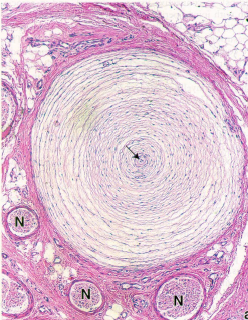

Q

Pacinian corpuscle

A

• deep dermis and hypodermis

• nerve fiber in the middle surrounded by flattened Schawnn cell lamellae that form the inner core of the corpuscle

• detect pressure and vibration

15

• Pacinian corpuscle